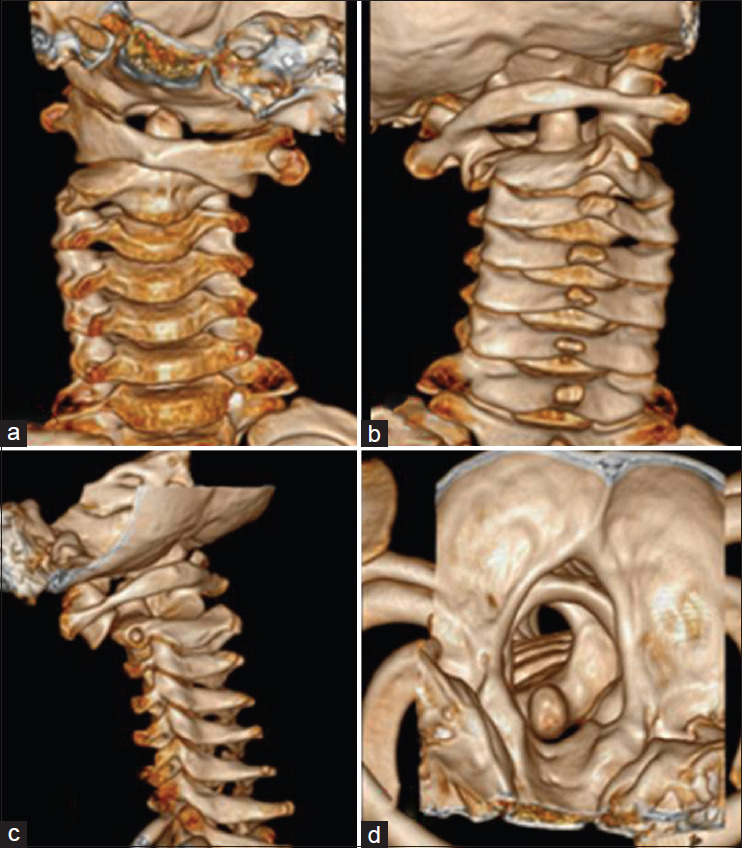

Atlanto-axial rotary subluxation (AARS) is rare but recognized as a significant cervical spine injury following a fall or physical impact on the head or neck in children aged 5-15 years. Trampoline use has been increasing among children, as have the trampoline-related injuries (TRI). We present a case series of AARS following trampoline injuries, highlighting clinical presentation, diagnosis, and management, especially in an emergency setting. We report four children with an average age of 8.5 years (range 6-12 years) presented to our hospital emergency service with neck pain and torticollis following a TRI. The diagnosis was confirmed through X-ray and computed tomography imaging, revealing Fielding and Hawkins type 1 AARS. Conservative treatment with analgesics, muscle relaxants, and a cervical collar led to recovery in three cases, while one required halter cervical traction for persistent deformity. All patients recovered completely, with no long-term complications. AARS in children is largely a type 1 injury with a favorable prognosis. Early recognition and management are crucial in preventing complications. The increasing incidence of neck injuries caused by trampoline use in children necessitates strict safety regulations regarding its use.